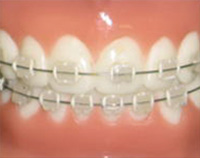

セラミックタイプ

歯と同じ色調のセラミックでできているため、装置が目立ちません。